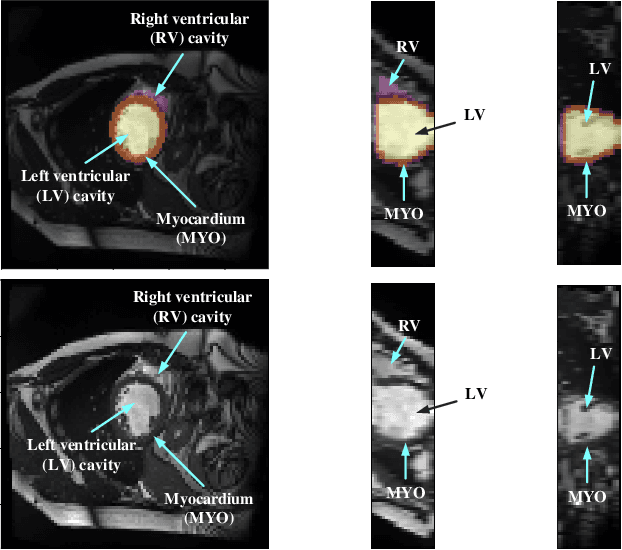

Abstract:Coronary artery disease (CAD) is the most common cause of death globally, and its diagnosis is usually based on manual myocardial segmentation of Magnetic Resonance Imaging (MRI) sequences. As the manual segmentation is tedious, time-consuming and with low applicability, automatic myocardial segmentation using machine learning techniques has been widely explored recently. However, almost all the existing methods treat the input MRI sequences independently, which fails to capture the temporal information between sequences, e.g., the shape and location information of the myocardium in sequences along time. In this paper, we propose a myocardial segmentation framework for sequence of cardiac MRI (CMR) scanning images of left ventricular cavity, right ventricular cavity, and myocardium. Specifically, we propose to combine conventional networks and recurrent networks to incorporate temporal information between sequences to ensure temporal consistent. We evaluated our framework on the Automated Cardiac Diagnosis Challenge (ACDC) dataset. Experiment results demonstrate that our framework can improve the segmentation accuracy by up to 2% in Dice coefficient.